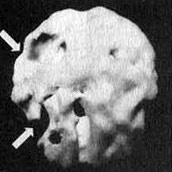

Мозг Эллен — последствия инсульта ![]() Трехмерное изображение поверхности мозга, вид слева. Обратите внимание на обширную «дыру», сформировавшуюся в результате инсульта в левой лобной доле 2. SPECT позволяет дать точную оценку состояния пациента, позволяющую предотвратить, заболевание в будущем. Нэнси, 59 лет, страдала от тяжелой депрессии, не поддававшейся лечению. Поступила в психиатрическую лечебницу, где ей было проведено исследование SРЕСТ. Каково же было мое удивление, когда оказалось, что в прошлом, при полном отсутствии соответствующих симптомов, она перенесла два обширных инсульта. Таким образом, стало понятно, что вызвало эту депрессию, не поддававшуюся обычному лечению. У 60 % пациентов, перенесших кровоизлияние во фронтальных долях, через год развивается тяжелая депрессия. Получив результаты SPECT, я немедленно проконсультировался с неврологом, который постарался определить причины инсультов, к которым нередко приводят, скажем, бляшки в сонных артериях или сердечная аритмия. Он пришел к выводу, что причиной инсультов у Нэнси стали тромбы, и назначил ей препараты, снижающие вязкость крови, чтобы предотвратить развитие новых инсультов. Мозг Нэнси — последствия двух инсультов ![]() Трехмерное изображение поверхности, вид сверху ![]() Трехмерное изображение поверхности, вид справа 3. С помощью SPECT можно получить информацию, помогающую врачу добиться понимания и сострадания к пациенту у членов его семьи. Фрэнк — состоятельный, хорошо образованный человек. Вскоре после того как ему исполнилось 70 лет, он стал забывчивым. Сначала он забывал мелочи, но со временем провалы в памяти стали прогрессировать, и он начал забывать значимые факты собственной биографии: где он живет, как зовут его жену и даже как зовут его самого. Жена и дети были не в состоянии понять, чем вызваны такие перемены, а его рассеянность и забывчивость их нередко раздражали. Результаты SPECT показали, что у Фрэнка на всей поверхности мозга отмечается резкое снижение активности, и особенно во фронтальных, париетальных и височных долях. Это была классическая картина синдрома Альцгеймера. Показав семье снимки и объяснив, что забывчивость Фрэнка имеет четкую физиологическую природу, я помог им осознать, что он не специально раздражает их, а серьезно болен. Впоследствии, вместо того чтобы упрекать его за забывчивость, близкие Фрэнка стали поддерживать его и разработали схемы, позволившие эффективнее бороться с трудностями, возникающими у всякого, кто вынужден жить рядом с человеком, страдающим болезнью Альцгеймера. Мозг Фрэнка — болезнь Альцгеймера ![]() Трехмерное изображение поверхности, вид сверху ![]() Трехмерное изображение нижней поверхности Обратите внимание на выраженное общее снижение активности, особенно в париетальных долях (см. стрелки, рис. слева) и в височных долях (см. стрелки, рис. справа). 4. SPECT позволяет проводить дифференциальную диагностику состояний со сходной симптоматикой. Я познакомился с Маргарет, когда ей было 68. Выглядела она неухоженно и неопрятно. Маргарет жила одна, и ее близких это очень беспокоило, так как у нее появились симптомы тяжелой деменции. После того как она чуть не сожгла дом, оставив включенной плиту, ее поместили в психиатрическую клинику, где в то время работал я. Из общения с ее близкими обнаружилось, что Маргарет часто забывала, как зовут ее собственных детей, и нередко, ведя машину, сбивалась с дороги и оказывалась в незнакомом месте. Водительские навыки ухудшились настолько, что после четырех небольших ДТП всёго за шесть месяцев у нее отобрали права. К тому времени, когда я встретился с ее близкими, многих из них эта ситуация уже утомила, и они были готовы сдать Маргарет в специализированный приют. Другие были против такого решения и хотели бы сначала обследовать ее в условиях стационара. На первый взгляд казалось, что Маргарет страдает болезнью Альцгеймера. Однако по результатам SPECT обнаружилось, что активность мозга в париетальных и височных долях не нарушена. Если бы у нее был синдром Альцгеймера, кровоток в этих областях должен был бы быть снижен. Вместо этого единственной патологией, которую нам удалось обнаружить на снимках SPECT, стала зона повышенной активности в глубокой лимбической области в центре мозга. Такая картина часто наблюдается у пациентов, страдающих депрессией. Из-за схожей симптоматики у больных старшего возраста нередко бывает трудно дифференцировать депрессию и болезнь Альцгеймера. Тем не менее при псевдодеменции (депрессии, которая выглядит как слабоумие) человек может выглядеть слабоумным, на самом деле таковым не являясь. Это чрезвычайно важный момент, так как, диагностировав болезнь Альцгеймера, мы даем близким ряд специальных рекомендаций и назначаем пациенту некоторые медикаментозные средства. Между тем, диагностируя депрессию, мы проводим агрессивную медикаментозную терапию антидепрессантами в сочетании с психотерапией. Результаты обследования Маргарет убедили меня в том, что ей следует назначить антидепрессант Wellbutrin (бупропион). Всего три недели спустя она уже была разговорчивой, ухоженной и охотно общалась с другими пациентами. Через месяц после госпитализации ее выписали домой. Перед выпиской она попросила меня написать письмо в автоинспекцию с просьбой вернуть ей водительские права. Поскольку мы с ней ездим по одному и тому же шоссе, я заколебался. Я сказал ей, что, если улучшение будет стойким и сохранится на протяжении по меньшей мере полугода, а сама она станет придерживаться рекомендаций врача и принимать все лекарства, я напишу письмо в автоинспекцию. Через полгода она оставалась в хорошей форме. Я сделал повторный SPECT — результаты показали полную норму. Тогда я обратился в автоинспекцию, и ей вернули права. Мозг Маргарет — псевдодеменция ![]() Трехмерное изображение снизу — активный мозг, до лечения. ![]() Трехмерное изображение снизу активный мозг, после лечения. |